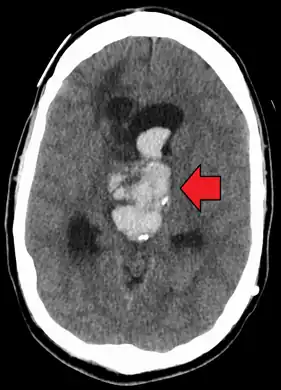

| Axial CT scan of a spontaneous intracranial hemorrhage | |

Evidence of intracranial hemorrhage on the left (brain cyst on right)

An acute bleed into a long-standing cystic mass within the brain. Arrow points to bleeding and mass.